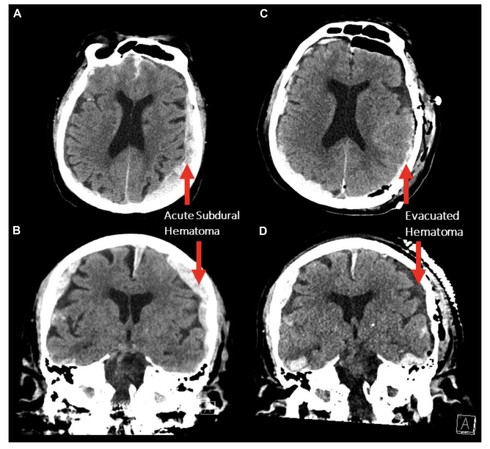

研究者たちは、脳出血により心停止に至った87歳の男性患者の死に際の脳波(EEG)を連続的に記録した。患者は転倒後に両側の硬膜下血腫を発症し、手術後にてんかん発作を起こした。その後、左脳の活動が停止し、次いで両半球の活動が抑制され、最終的に心停止に至った。